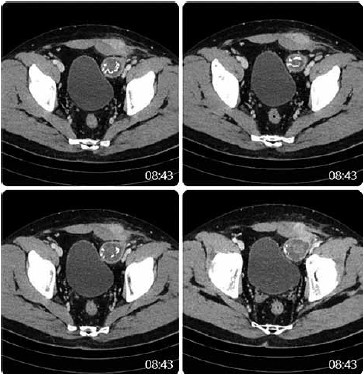

Homem de 35 anos foi submetido a uma herniorrafia inguinal esquerda pela técnica aberta/convencional de Lichtenstein. No 15º dia de pós-operatório, apresentou dor no local da incisão e sinais flogísticos locais. Foi realizada tomografia computadorizada (a seguir demonstrada).

(Arquivo pessoal; imagens usadas com autorização)

O diagnóstico do paciente é